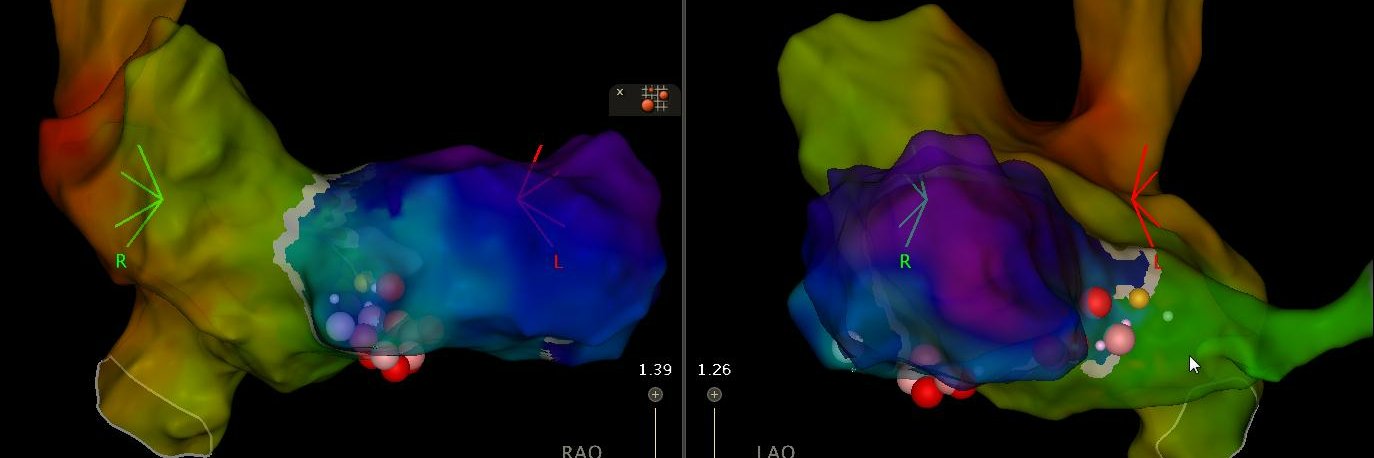

@DrRoderickTung In the advent of wider WACAs with some PFA systems; whats your threshold of finishing a PWI when an isthmus remains? Another area of uncertainty of whats safe to leave.

What’s the obsession with PWI in AF ablation? It may appear “safe & easy” @drjohnm BUT no randomised evidence & there is downside #TWIC Oct 10